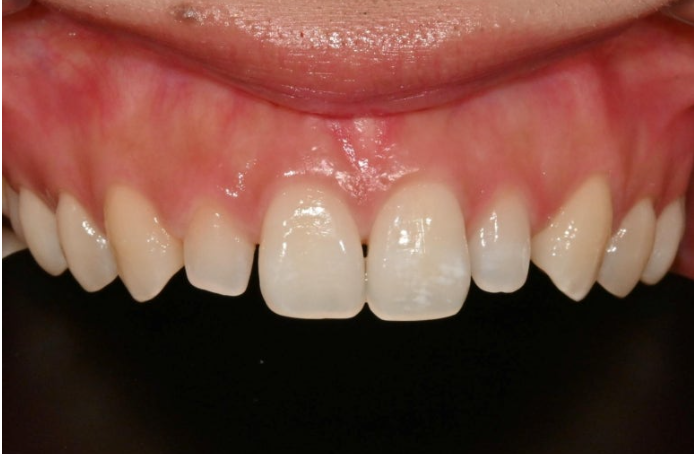

왜소치에 각각 무삭제라미네이트 시술 후 모습입니다.

극강의 얇은 두께로 인해 본래 치아색이 우러나와 생기는 우윳빛 투명감은 젤라미의 특징입니다

표면의 아주 옅은 반점치 무늬가 보이시나요?

주변 치아와 질감 뿐 아니라 표면의 미세 무늬까지 구현하여 이질감을 없애 자연스럽게 어우러지도록 합니다.